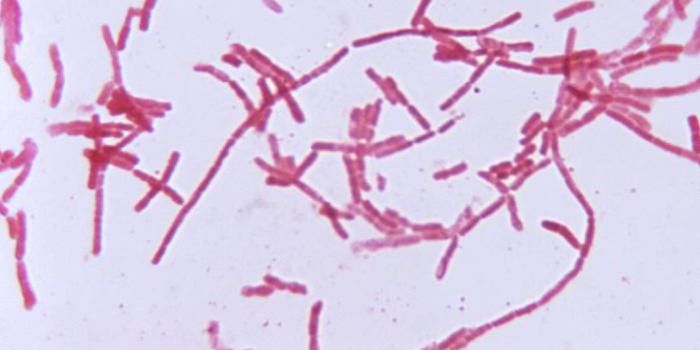

JUL 15, 2015MicrobiologyClostridium difficile is most commonly referred to as a healthcare-associated infection (HAI), with at risk-populations ...